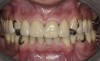

Figure 2  Intraoral occlusal view of maxillary dentition with the existing removable prosthesis presenting excessive signs of wear.

Figure 2

Initial examination revealed a partial edentulous patient with extensive wear of the maxillary anterior teeth and moderate wear in the mandibular teeth (Figure 1, Figure 2, Figure 3 , Figure 4, Figure 5, Figure 6 and Figure 7). The patient's maxillary and mandibular RPDs also showed excessive wear and multiple signs of fractures (Figure 2 and Figure 3). The patient had been wearing a mandibular nightguard for 8 years.